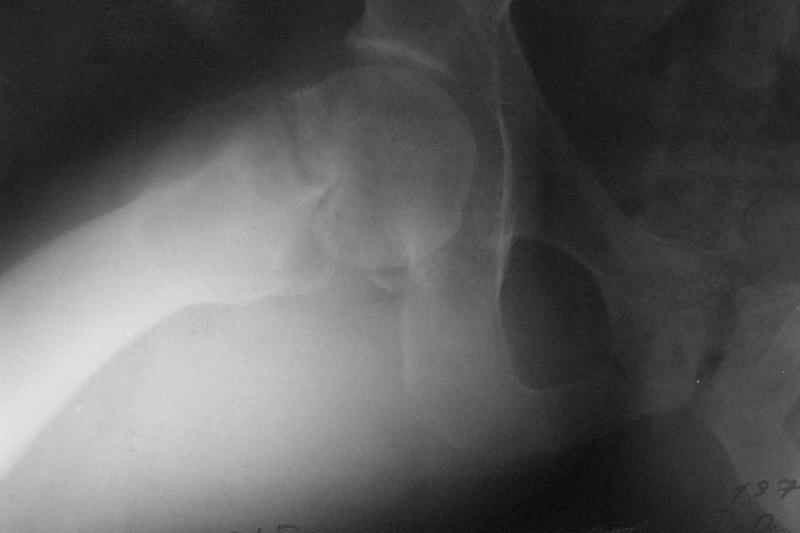

Stephen Kottmeier 17 Октябрь 2005, 21:05

friend

dhs will not correct improper biomechanical environment and may further compromise vascular

integrity consider establish vascular status via mri

and if viable follow with proximal valgus osteotomy

case provided s/p failed fixation

I think that this 31 yo deserves a try with valgus osteotomy, as so nicely illustrated by stephen kottmeier. However, I'd do it no matter what an MRI shows - thus why bother with the MRI? (What sort of data support MRI's ability to predict segmental collapse?)